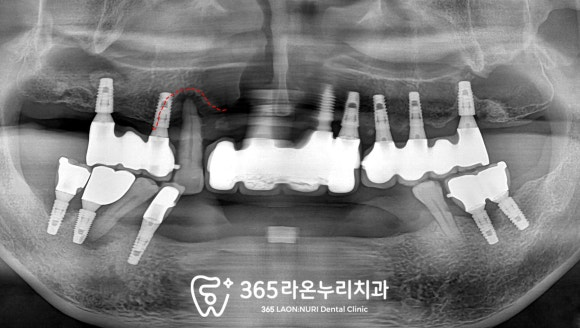

파노라마를 찍어

눈에 보이지 않는 부분도 살펴봐야겠죠?

방사선량을 최소로 한

엑스레이 장비를 이용하여

촬영해 보았습니다.

엑스레이를 보면

흔들리고 염증이 있던

오른쪽 위 송곳니(#13)는

치아 뿌리 끝까지 골소실 소견을 보이고 있어

빠른 개선이 필요하겠습니다.